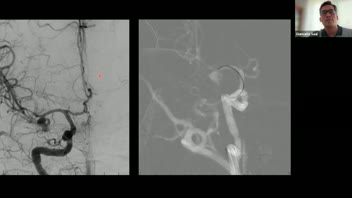

Endovascular Management of Giant Intracrianal Aneurysms; Dr. Angel Ferrario.

Management of Giant Cerebral Aneurysms